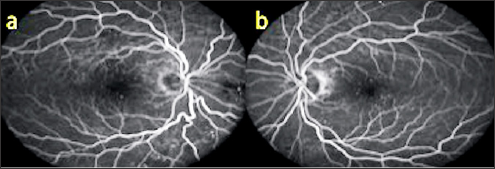

Figure 5: Fundus appearance in both eyes (a,b).

A 50 year old male presented with complaints of blurred vision. The VA was 9/10 in both eyes with no refractive correction need. Anterior segment biomicroscopic examinations were of course normal in both eyes. IOPs were 14 mmHg in both eyes. In the fundus examination, several angioid streaks and light-dark colored bands were seen in the per papillary region in both eyes (Figure 5a & 5b). Wrinkles were observed in choroid, RPE and neurosensory layers in OCT (Figure 6a & 6b). In FFA, more prominent angioid streaks were observed around the optic disc in the left eye, and hyper fluorescence due to RPE cracks was observed (Figure 7a & 7b). Microperimetry (MP) revealed that sensitivity was normal in folding areas while sensitivity was decreased in areaswith RPE defect (Figure 8a & 8b). Radiologic imaging studies and laboratory examinations for orbital, intracranial and systemic pathologies were within normal limits. CFs associated with angioid streaks was diagnosed.

Figure 6: OKT images (a,b).

Figure 7: FFA images (a,b).